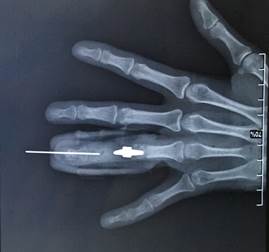

Операционный доступ осуществлялся через тыльную поверхность средней фаланги. Имплантат вводился в рану, замещая дефект, и фиксировался к дистальному отломку кости с использованием спицы. В проксимальный конец имплантата закреплялась дистальная часть протеза межфалангового сустава с применением костного цемента, при этом проксимальная часть протеза фиксировалась в проксимальный отломок кости без особенностей (рис. 3).

Через двадцать четыре недели после операции было отмечено полное заживление послеоперационной раны без признаков воспаления. Процесс заживления соответствовал установленным срокам и объёму проведённого вмешательства. Вторичных деформаций выявлено не было. При выполнении движений реконструированным пальцем болевые ощущения отсутствовали, что подтверждало успешное восстановление функции (рис. 4).

Рис. 4. Демонстрация внешнего вида кисти через 1 год после установки углеродного импланта

Источник: фото из архива автора.